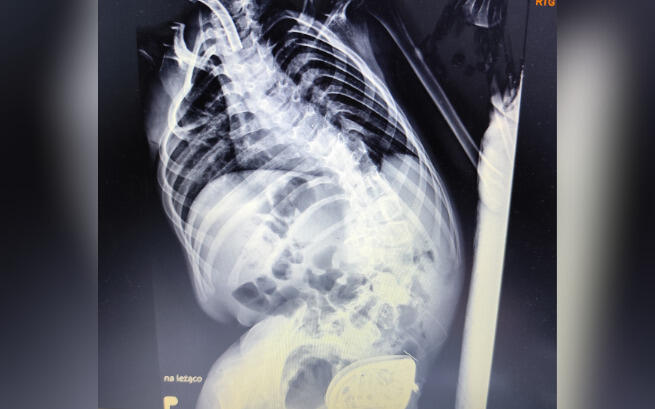

Byliśmy na konsultacji ortopedycznej, żeby sprawdzić, czy można coś zrobić z kręgosłupem, bo skrzywienie postępuje w zastraszającym tempie, ale lekarz zdecydowanie stwierdził, że powikłania pooperacyjne mogłyby być dla niej śmiertelne.

Także pozostaje nam tylko intensywna rehabilitacja i codzienne patrzenie na nieunikniony postęp choroby...